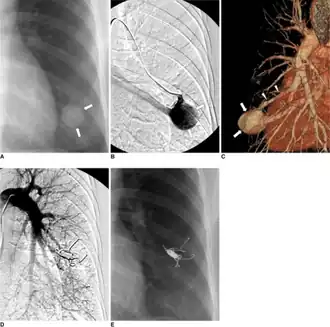

Pulmonary arteriovenous malformation-a) X-ray b) left selective pulmonary arteriogram c) CT angiogram demonstrates pulmonary arteriovenous malformation arrows d) after embolotherapy (placing four Nester coils) e) 19 months after embolotherapy complete disappearance pulmonary arteriovenous malformation shadow